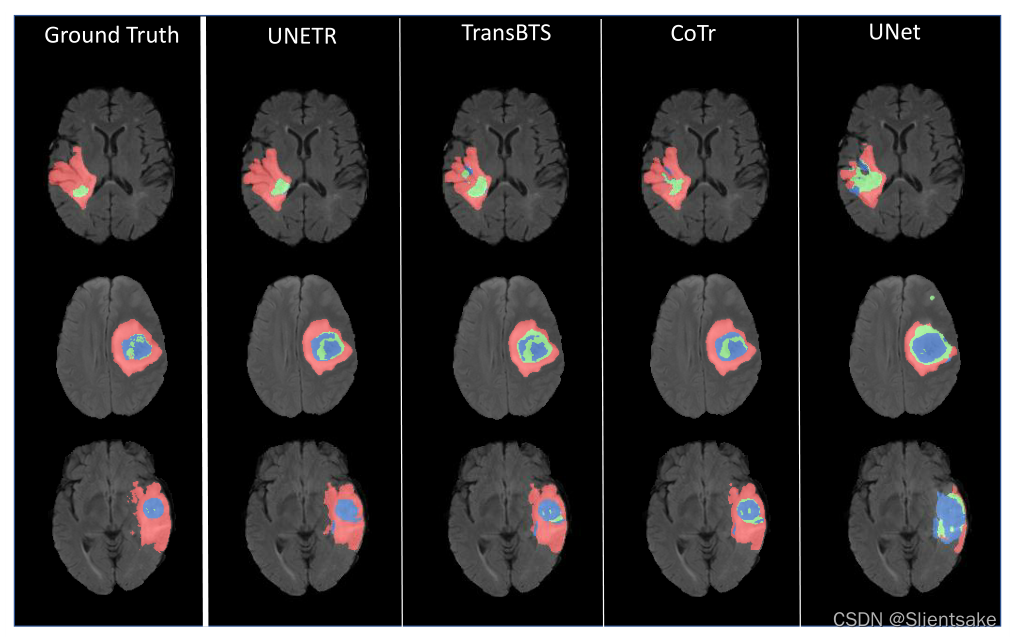

多器官分割的定性比较如图3所示。UNETR提高了腹部器官的分割性能。模型学习远程依赖的能力在第3行(从上面开始)很明显,其中nnUNet混淆了肝脏和胃组织,而UNETR成功地描绘了这些器官的边界。在图3中,第2行和第4行显示肾脏和肾上腺对周围组织的清晰检测,这表明UNETR捕获了更好的空间上下文。与基于二维Transformers的模型相比,UNETR展示了更高的边界分割精度,因为它准确地识别了肾脏和脾脏之间的边界。可见胆囊在第二排,肝脏和胃在第三排,门静脉对肝脏在第五排。在图4中,给出了在MSD数据集上对脑肿瘤分割的定性分割比较。具体来说,模型在捕捉肿瘤的细粒度细节方面表现得更好。

图4:UNETR有效地捕捉细分输出的细粒度细节。